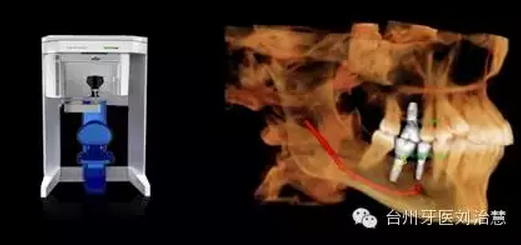

五、種植牙

145.png

種植牙的精確定位及術(shù)前輔助設(shè)計。華西口腔醫(yī)學(xué)院李娜、王虎等曾于2012年發(fā)表論文,旨在探討上頜竇生理及病理性CBCT 影像表現(xiàn),為上頜竇提升術(shù)解剖定位和操作入路提供參考依據(jù)。研究指出,CBCT 能夠準(zhǔn)確地顯示完整的上頜竇影像,利用 CBCT 確定解剖定位標(biāo)志,確定上頜竇提升手術(shù)路徑和方式,更符合安全、準(zhǔn)確、微創(chuàng)的口腔種植理念。該文發(fā)表于《中國口腔種植學(xué)雜志》2012年第3 期。

總之,CBCT數(shù)秒內(nèi)完成對患者的掃描,實現(xiàn)對種植位點的快速評估,并使用嵌入工具測量可以利用的骨量,發(fā)現(xiàn)隱藏的病灶。使用自動神經(jīng)管標(biāo)記工具描繪出神經(jīng)管走行。直觀顯示骨內(nèi)阻生牙的精確位置,確定臨牙位置及毗鄰重要結(jié)構(gòu),包括神經(jīng)管、上頜竇壁和骨皮質(zhì)邊界。